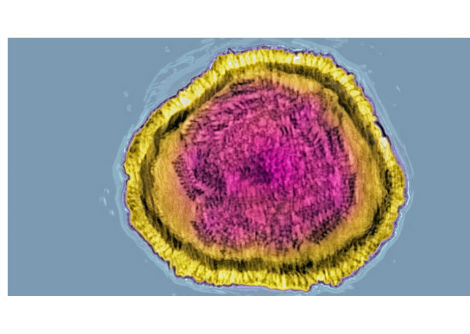

لكن عمليات زراعة كبد الخنازير تُشكل تحديًا خاصًا، كما قال وانغ: "الكبد معقد للغاية". فعلى عكس القلب الذي يضخ الدم والكلى التي تُنتج البول، يتميز الكبد بقدرة فائقة على الإنجاز. يقوم هذا العضو المفصص بالعديد من الوظائف، بما في ذلك إزالة السموم من الدم، وإنتاج العصارة الصفراوية للمساعدة في الهضم، والتخلص من خلايا الدم الحمراء القديمة، وتخزين الطاقة، وإنتاج جزيئات تساعد على تخثر الدم.

في عام 2023، حاول باحثون في جامعة بنسلفانيا استخدام كبد خنزير معدل وراثيًا كجهاز احتياطي، حيث تم توصيل العضو خارجيًا بشخص توفي مؤخرًا. وتمكن الفريق من تدوير دم الشخص من خلال كبد الخنزير، وهي خطوة نحو استخدام العضو للقيام مؤقتًا بمهام الكبد لدى مرضى فشل الكبد. وفي الحالة الجديدة، أدخل الجراحون الكبد إلى داخل الجسم. بدأ الفريق بخنزير باما مصغر، حُذفت منه بعض جينات الخنزير، وأُضيفت إليه جينات بشرية. تلعب هذه الجينات دورًا في رفض عملية الزرع؛ وكان الهدف من هذه التعديلات تقليل احتمالية فشل عملية الزرع.